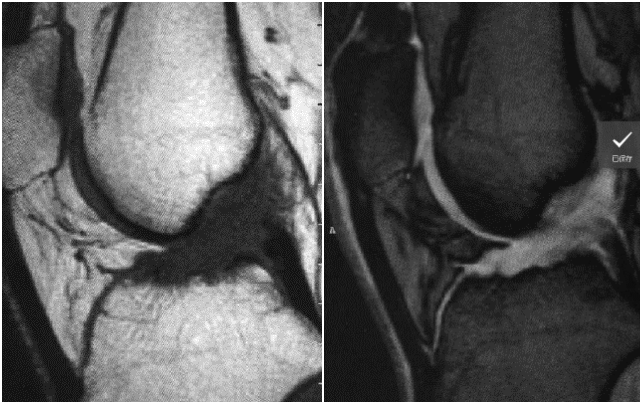

男,64 岁,右侧前交叉韧带损伤,止点撕脱骨折

女,50 岁,胫骨髁间隆突撕脱骨折,前交叉韧带部分撕裂

病例 1:

男,50 岁,前交叉韧带部分损伤,T1 及 T2 加权序列,韧带信号明显增强,形状略不规则,纤维束部分仍连续

病例 2:

女,54 岁,左膝关节前交叉韧带部分撕裂,左侧胫骨上段骨折伴骨髓水肿,矢状面 T1 加权序列,冠状面及矢状面 T2 加权序列,韧带信号增高,部分纤维束连续